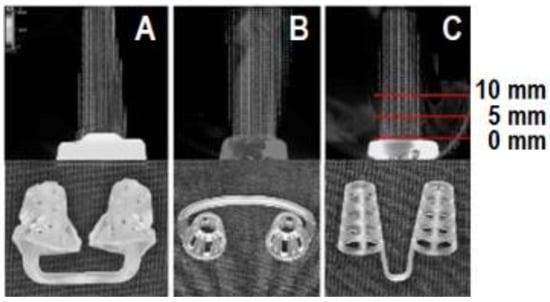

2.2. Nasal Dilators

2.3. Velocity Measurement by Visualization

3.1. Velocity Measurement by Visualization

| 0 mm | 2687.3 | 41.1 | 3203.7 | 122.9 | 2748.9 | 140.2 | 2046.6 | 121.1 | 7534.4 | <0.001 | Mute with hole < No appliance < Nose Cones< NBS |

| 5 mm | 2686.4 | 36.2 | 3146.5 | 111.1 | 2967.8 | 82.5 | 2186.4 | 61.9 | 13,781.3 | <0.001 | Mute with hole < No appliance < Nose Cones < NBS |

| 10 mm | 2661.6 | 46.8 | 3180.1 | 82.5 | 2891.9 | 109.8 | 2324.4 | 62.5 | 12,144.3 | <0.001 | Mute with hole < No appliance < Nose Cones < NBS |